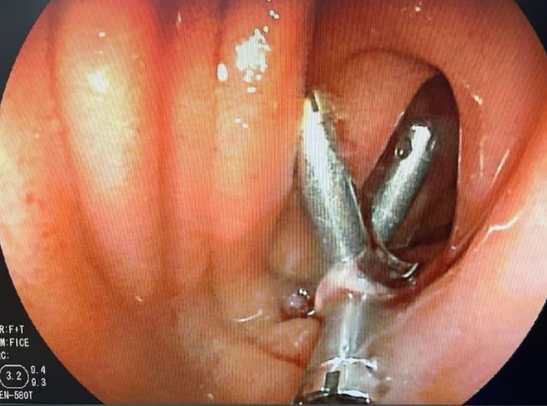

唐成祥醫(yī)生與患者家屬溝通之后,馬上為患者王大姐安排了小腸鏡手術(shù)。術(shù)中,經(jīng)肛小腸鏡的時候,發(fā)現(xiàn)回腸腺段有一個微小的破潰,魚刺已穿破小腸壁到達腹腔,形成了一個潰瘍。唐成祥醫(yī)生用鈦夾封住了創(chuàng)面。緊接著聯(lián)系了外科醫(yī)生做了個腹腔鏡,找到魚刺并取出。

唐成祥醫(yī)生表示,患者王大姐積極配合治療與檢查,所幸腸腔并沒有出現(xiàn)壞死,通過小腸鏡把創(chuàng)面封堵住,避免了外科手術(shù)的部分小腸切除。